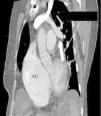

Una causa atípica de hipertensión pulmonar en el anciano

An atypical cause of pulmonary hypertension in the elderly